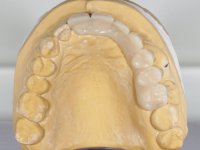

A temporary acrylic bridge made in the laboratory with 7 elements was made, with teeth 11,21, 25 and 26 as pillars. The old bridge was removed and tooth 24 was extracted. The provisional bridge after relining was cemented in the mouth. Two implants were placed in the teeth 22 and 24 and 3 months after this intervention an impression was made to make a temporary bridge screwed over the implants and cemented to the teeth. The bridge was placed in the mouth and teeth 25 and 26 were extracted. 3 months later, surgery was performed to fill the maxillary sinus and 6 months later the implant was placed in the location of tooth 26. After osseointegration of this implant, the final impression was made for the final work. The bridge over the implants was permanently screwed on and the bridge over the teeth was cemented with resin-reinforced glass ionomer cement.